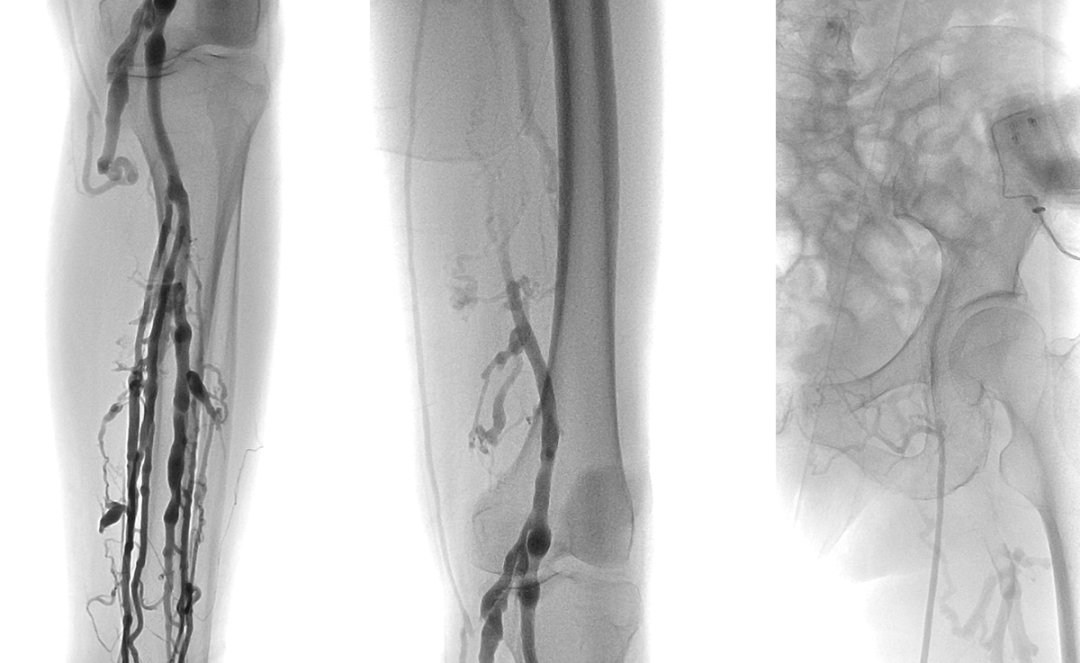

左腘静脉穿刺置鞘,对近端血栓行AngioJet喷注尿激酶后吸栓,吸栓后股浅静脉恢复通畅

复查造影:股深静脉内血栓,股总静脉血流瘀滞,左髂静脉狭窄行PTA

Simon导管翻山后导丝进入股深静脉,造影明确股深静脉血栓范围

股深静脉吸栓后通畅,于左髂静脉置入14*80mm支架,复查造影血流均通畅